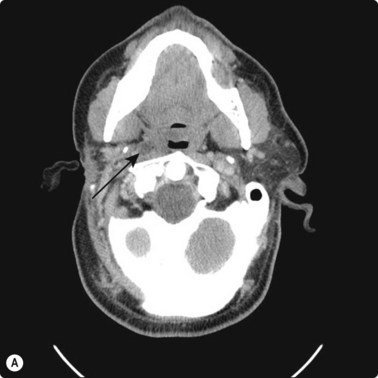

CT scanning

There are very few areas of the body which cannot be biopsied under CT control, and extremely small lesions can be sampled. Focal masses of several millimeters within the lung and skull base (Fig. 3.2) can be biopsied and retroperitoneal biopsies are limited only by availability of needles long enough to traverse the abdomen of large patients. Traversing with fine needles offers fewer risks compared with the larger-caliber needles.7 CT gantry tilt also further facilitates lesion access where appropriate.

image image

Fig. 3.2 (A) Circular low dense lesion right retropharyngeal node in a patient post right parotidectomy and radiotherapy for parotid squamous cell carcinoma. (B) Coaxial fine needle aspiration biopsy technique under CT control confirmed nodal recurrence. The utility of CT biopsy techniques and fine needle aspiration biopsy helped direct this patient’s management.

Localization of the needle tip within a lesion is very accurate with CT (Fig. 3.3). It provides detailed cross-sectional images of the body which are not limited by the same physical properties as are ultrasound images, such as interference from bowel gas and bone.